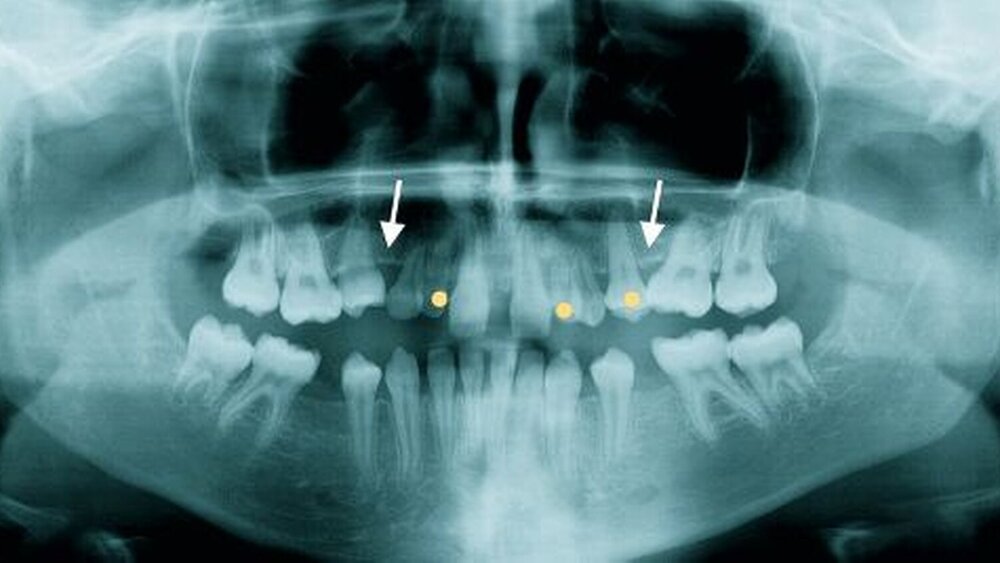

Eine zehnjährige Patientin wurde uns von der Kieferorthopädin zur Wertung von möglichen chirurgischen Maßnahmen bei multiplen Nichtanlagen der Zähne 14, 13, 12, 22, 23, 24, 25, 45 vorgestellt (Abbildung 1 A-D). Aufgrund des Vorhandenseins der Milchzähne 73 und 83 sowie eines im Unterkiefer angelegten Zahnes 35 bei nicht angelegten Zähnen 12 und 22 sowie 24 und 25 empfahlen wir bei Vorhandensein von jeweils einem Prämolaren in den Quadranten I und IV das folgende chirurgische Vorgehen: Transplantation des Zahnes 35 nach 025, Transplantation des Milchzahnes 73 nach 022 und Transplantation des Milchzahnes 83 nach 011 (Abbildung 2).

4. der noch tief retinierte Zahn 35 wurden schonend entfernt und an die vorgesehenen Stellen in regio 012, 022 sowie 025 transplantiert. Die Abbildung 3 zeigt das postoperative Ergebnis der drei autogenen Transplantationen klinisch (A bis C) und röntgenologisch (D).

Die inzwischen zwölf Jahre alte Patientin stellte sich erneut im Februar 2008, also 1,5 Jahre nach dem Eingriff, zur Kontrolle bei uns vor. Die Zähne stellten sich klinisch reizlos und ohne Lockerungsgrad (Abbildungen 5 A bis D) oder fortschreitende Resorptionszeichen (Abbildung 6) dar. Im Bereich des transplantierten Zahnes 25 ist es zu einem klinisch signifikanten Zuwachs des Alveolarknochens sowohl in der horizontalen als auch vertikalen Dimension gekommen (Abbildung 6). Dieser Knochenzuwachs ist nahezu vergleichbar mit dem auf der gesunden Seite im I. Quadranten, wo es durch den natürlichen Zahndurchbruch des Zahns 15 zu einer ähnlich guten Alveolarfortsatzknochenbildung gekommen ist.

Die autogene Milchzahntransplantation stellt eine Methode dar, die in der Literatur kaum Erwähnung findet. Wissenschaftlich fundierte Zahlen zur Erfolgsrate der autogenen Milchzahntransplantation liegen aufgrund der geringen Fallzahlen in der Literatur nicht vor, wie dies etwa bei der autogenen Transplantation von bleibenden Zähnen der Fall ist [Natiella et al, 1970; Nolte et al., 2006]. Es finden sich aktuell lediglich Fallberichte, wie der hier vorgestellte, in denen über die zum Teil guten Erfolge dieser Methode berichtet wird [Pohl, 2001; Butz, 2008; Sönmez, 2008]. Als besonders geeignet für den Eingriff gelten die unteren Milch eckzähne [Schafigh, 2005]. Nach unseren klinischen Erfahrungen kann bei Nichtanlage oder Verlust von bleibenden oberen Schneidezähnen die für die Entwicklung des Kieferknochens wichtige Zeit vom 10. bis 14. Lebensjahr mit der Technik der autogenen Milchzahntransplantation als temporärer Lückenfüller erfolgreich überbrückt werden. Dies erscheint vollkommen ausreichend, um diese wichtige Wachstumsphase der Kiefer in der Entwicklung physiologisch zu stimulieren und dem Kind dadurch eine schleimhautgetragene Prothese mit all ihren psychischen Belastungen sowie ungünstigen Auswirkungen auf das Kieferwachstum in dieser Zeit zu ersparen. Durch das Wegfallen einer schleimhautgetragenen Prothese ist der Gewinn an Lebensqualität für die kleinen Patienten sehr hoch. Die Zustimmung der Patienten sowie derer Eltern kann daher als ausgezeichnet bezeichnet werden, sodass der Eingriff auch bei vorzeitigem Verlust der Milchzähne immer mit einer Verbesserung der knöchernen Verhältnisse verbunden sein wird. Die Morbidität der kleinen Patienten ist insgesamt als gering einzustufen. Der psychologische Effekt auf die Kinder und ihre Eltern kann gar nicht hoch genug eingeschätzt werden. Die Intention dieses Artikels war es, auf die Methode der autogenen Milchzahntransplantation aufmerksam zu machen, da sie insbesondere bei jugendlichen Patienten mit Nichtanlagen oder traumatischem Verlust von Zähnen eine bewährte Technik des Zahnersatzes darstellt, um den Kindern in der Zeit vom 10. bis zum 14., möglicherweise auch bis zum 16. Lebensjahr eine schleimhautgetragene Prothese zu ersparen. In dem hier vorgestellten Fall sind die Milchzähne seit 1,5 Jahren in situ und haben zu einem beachtlichen Knochenanbau sowohl in der horizontalen als auch vertikalen Dimension beigetragen, was die osteoinduktiven Eigenschaften dieser Methode unterstreicht. Das zum Beispiel bei Nichtanlagen ausbleibende Alveolarfortsatzwachstum kann durch autogene Zahntransplantate, seien es bleibende Zähne oder Milchzähne, sehr wohl stimuliert werden (Abbildung 6). Je nach zeitlichem Verlauf der Resorption der transplantierten Milchzähne kann dann später im Alter von 14 bis 16 Jahren mit der Implantation begonnen werden, ohne dass ein aufwendiger Knochenaufbau notwendig wird, der in der Regel ohnehin die prognostisch ungünstige Technik der Auflagerungsosteoplastik verlangt.